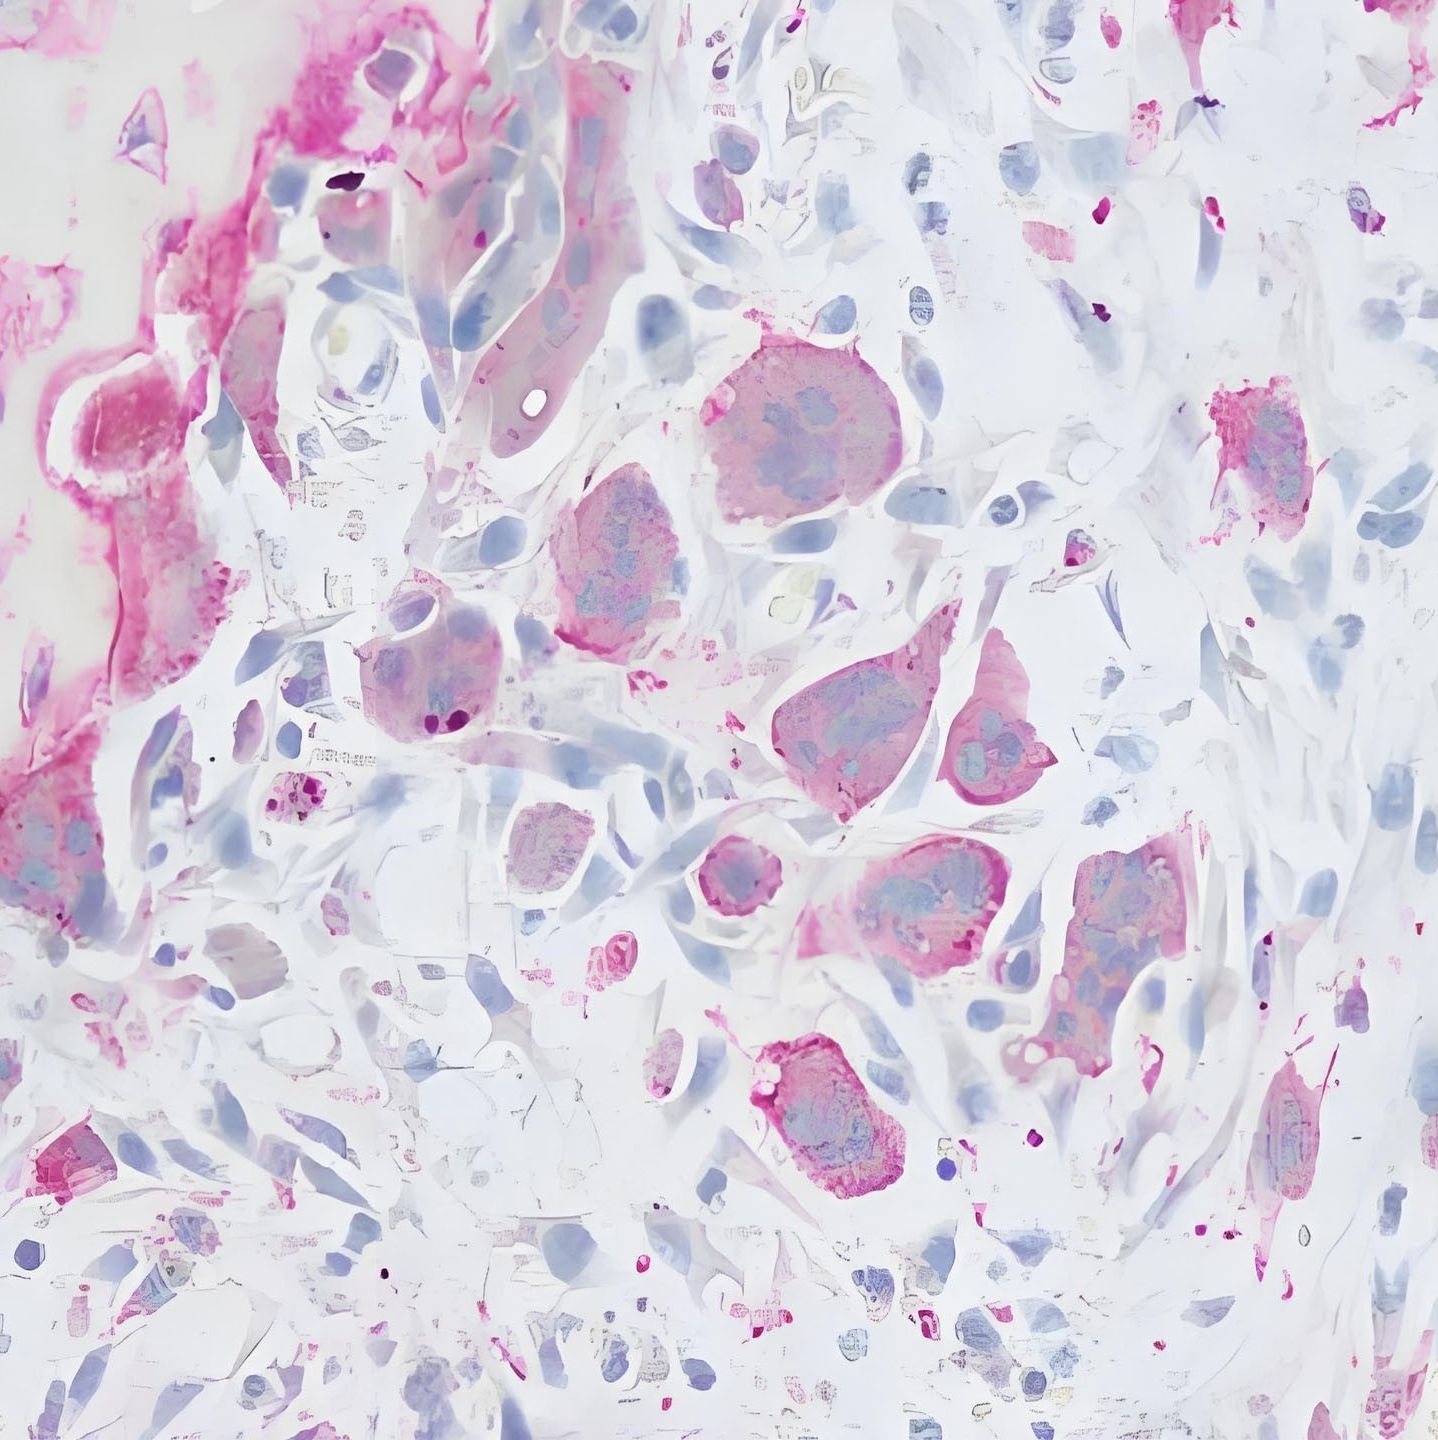

酸性磷酸酶 (Acid Phosphatase,ACP) 分布极广泛,遍布各种组织,主要存在于细胞的溶酶体内,所以常作为溶酶体的标志酶,溶酶体外的酸性磷酸酶存在于内质网和胞质内。各种动物中的酸性磷酸酶各有不同,酸性磷酸酶的适宜 pH 值为 4.5~5.5, 存在于正常人肺泡巨噬细胞和白血病人脾脏的抗酒石酸酸性磷酸酶 (Tartrate-resistnt Acid Phosphatase, TRAP) 均在细胞滤泡中,并不是释放入血液,血液中的 TRAP 绝大多数来源于破骨细胞,因此可以通过测量血液中的 TRAP 了解破骨细胞的功能状态。 EnkiLife 抗酒石酸酸性磷酸酶(TRAP)染色液以萘酚 AS-BI 为底物,在酸性 pH 下被酸性磷酸酶水解释放出磷酸和萘酚,萘酚与重氮盐偶联生成有色产物,定位于细胞质中,若细胞内的 ACP 有抗酒石酸的活性,则呈阳性反应,可用于新鲜血涂片、细胞涂片、冰冻切片。该试剂仅用于科研领域,不适用于临床诊断或其他用途。

1. 前言了解活体的骨代谢状态是研究相关细胞生理活性的一个有效方法。对骨组织进行碱性磷酸酶(ALP)染色后可以了解成骨细胞的骨形成情况,对骨组织进行抗酒石酸酸性磷酸酶(TRAP)染色可以了解破骨细胞的骨吸收情况。若在同一切片上进行双重染色就能同时了解两者的情况。另外,它有一个优点是在脱钙标本里,只要可以双重染色,无需专用的设备,仅用一般的设备就可以方便地观察到骨代谢。在此前提下,我们需要研究探讨双重染色的可行性。2. 标准标本的制作用树脂包埋法或冻结切片法制成的标本作为标准标本,与脱钙